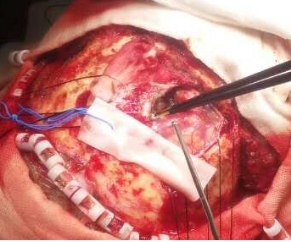

月11日上午9点30分,我院神经外科王冰主任亲自主刀,带领神经外科专业医疗团队,在麻醉科医师的协助下,为郭大爷行“额部肿瘤切除术+颅骨修补术”。术中发现病变组织竟然已侵蚀颅骨(图2),向头皮外生长,与脑组织及硬脑膜紧密粘连,侵犯矢状窦,手术过程中稍不留意就会出现大出血,风险极大。王冰主任凭借自己多年的临床经验及手术经验,临危不惧。经过近3个小时的不懈努力,终于完整清除郭大爷被肿瘤侵犯的脑组织、脑膜及颅骨(图3)。手术非常顺利。术后郭大爷神志清楚,恢复良好。现已转出神经外科监护室,到普通病区继续康复治疗。

图2 图3

(术中见肿瘤) (切除肿瘤后)